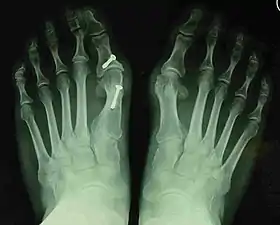

- For recurrence correction after osteotomy procedure (Fig. 8)

Late deformity recurrence can happen after osteotomy (bone-breaking) procedures because osteotomy surgeries do not specifically stabilize first metatarsal bone.